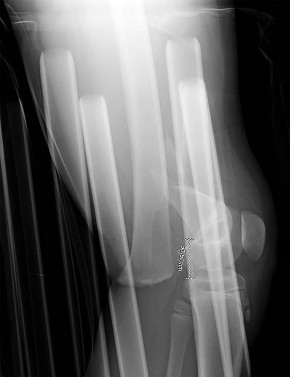

A 4-year-old girl is evaluated for severe bowing of her left leg. Radiographs reveal a prominent physeal step-off with depression of the medial tibial plateau, consistent with Langenskiöld stage IV infantile Blount's disease. What is the most appropriate management?

Explanation